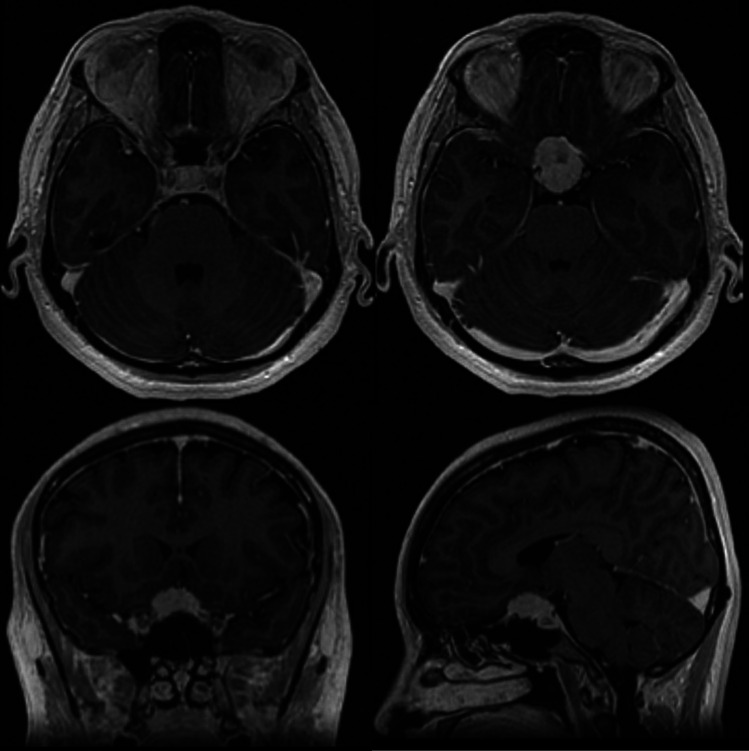

Abstract Image

Purpose: Optic canal decompression is a surgical option in anterior skull base tumors with optic nerve involvement. Meningiomas may grow into the optic canal even without evidence of involvement on MRI studies. We aim to investigate the effect of routine optic canal unroofing performed by skull base trained surgeons versus general neurosurgeons on the postoperative visual outcomes in anterior skull base meningiomas.

Results: Out of 709 patients who underwent craniotomies for anterior skull base meningiomas, 94 patients showed optic nerve involvement on MRI. In total, 59 cases were treated by skull base trained surgeons and 35 by general neurosurgeons. Optic canal decompression was performed in 65% of the patients. There was no significant difference between patients treated by skull base surgeons and general neurosurgeons in terms of postoperative permanent complications. In patients with tuberculum sellae or anterior clinoid process meningiomas, postoperative secondary deterioration of visual acuity occurred in 40% (n = 10) of the cases treated by general neurosurgeons versus 11% (n = 4) in the group treated by skull base trained surgeons. In cases with a preoperative visual acuity of 0.2 or lower (35%, n = 33), 42% (n = 14) reached a best postoperative visual acuity of 0.5 or higher. Nineteen (20%) cases presented with functional blindness preoperatively. Of these, nine (47%) cases showed significant vision improvement postoperatively. Multivariable linear regression analysis revealed that patients with higher preoperative visual acuity reached a higher best visual acuity postoperatively.